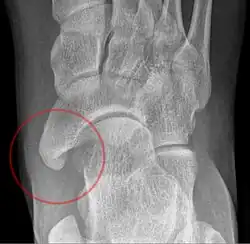

-

From left to right: Type 1, 2 and 3 -